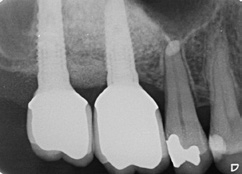

Die allgemeinmedizinisch gesunde Patientin befand sich aufgrund ihrer Grad-IV-Parodontitis seit 2013 in einem engmaschigen parodontalen Recall. Trotz der starken parodontalen Destruktion lagen stabile Verhältnisse vor. Ende 2016 stellte sich die Patientin mit Beschwerden an Zahn 16 vor. Dieser reagierte negativ auf die Sensibilitätsprobe und wies einen Furkationsgrad 3 auf. Zudem zeigte sich röntgenologisch eine apikale Aufhellungszone. Da bei dem Nachbarzahn 17 ebenfalls ein Furkationsgrad 3 bei einem Lockerungsgrad I vorlag, wurden in Absprache mit der Patientin Zahn 16 und 17 operativ entfernt. Die Patientin wünschte eine festsitzende, implantologisch-prothetische Rehabilitation und lehnte eine herausnehmbare Versorgung ab.

Nach einer Abheilzeit von 10 Wochen wurde im Rahmen der präimplantologischen Diagnostik aufgrund der Komplexität der Defektsituation im 1. Quadranten regio 16 und 17 neben der klinischen Untersuchung eine DVT-Aufnahme angefertigt. Es zeigte sich ein transversaler und vertikaler Knochendefekt mit einer Restknochenhöhe von teilweise nur 1 mm. Zu beachten war auch die Höhe des Knochenlagers, das sich teilweise auf Höhe des Apex des Nachbarzahnes 15 befand (Abb. 1a und b). Dieser dreidimensionale Defekt sollte durch einen externen Sinuslift nach kranial sowie eine ventrale horizontale auflagernde Augmentation ausgeglichen werden. Hierfür wurde mit dem DICOM-Datensatz der DVT-Aufnahme ein virtuelles Modell hergestellt, welches die Planungsgrundlage für das Augmentationsvolumen darstellte (Abb. 1c). Anhand dieser Daten und in Abstimmung mit dem Behandler stellte die ReOss GmbH ein patientenindividuell gedrucktes Titangitter für die Augmentation her.